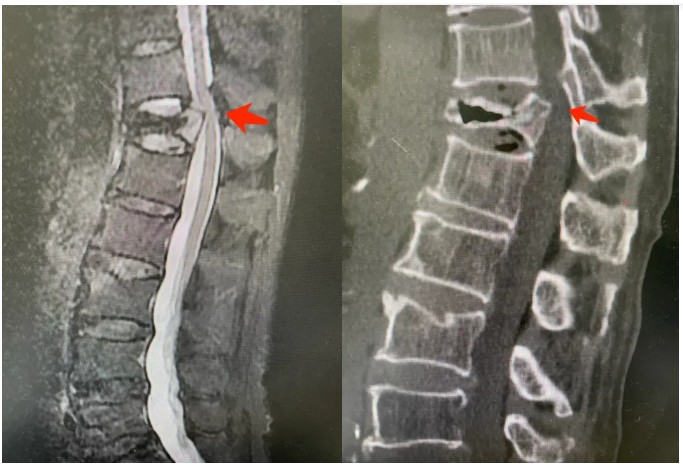

来到徐州一院就诊后,经影像学检查发现,李先生为胸12椎体陈旧性骨折并发Kummell病,椎体内部出现坏死和塌陷,并对脊髓神经造成压迫。

术前检查显示骨折未愈合,压迫脊髓神经

术后复查ct可见术前压迫解除,骨折处得到支撑